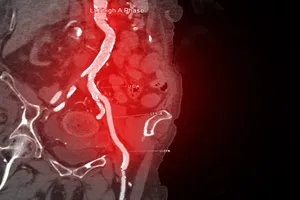

6. 폐색전증

혈전이 폐동맥을 막아 폐혈관이 막히면 폐에 충분한 산소가 공급되지 않아 호흡곤란, 흉통 등이 발생합니다. 이러한 폐색전증은 혈전 용해제 투여를 통해 혈전을 녹이고, 항응고제를 투여하여 새로운 혈전 생성을 억제하며, 필요에 따라 수술을 통해 혈전을 제거하거나 폐혈관을 넓히는 시술을 시행합니다.